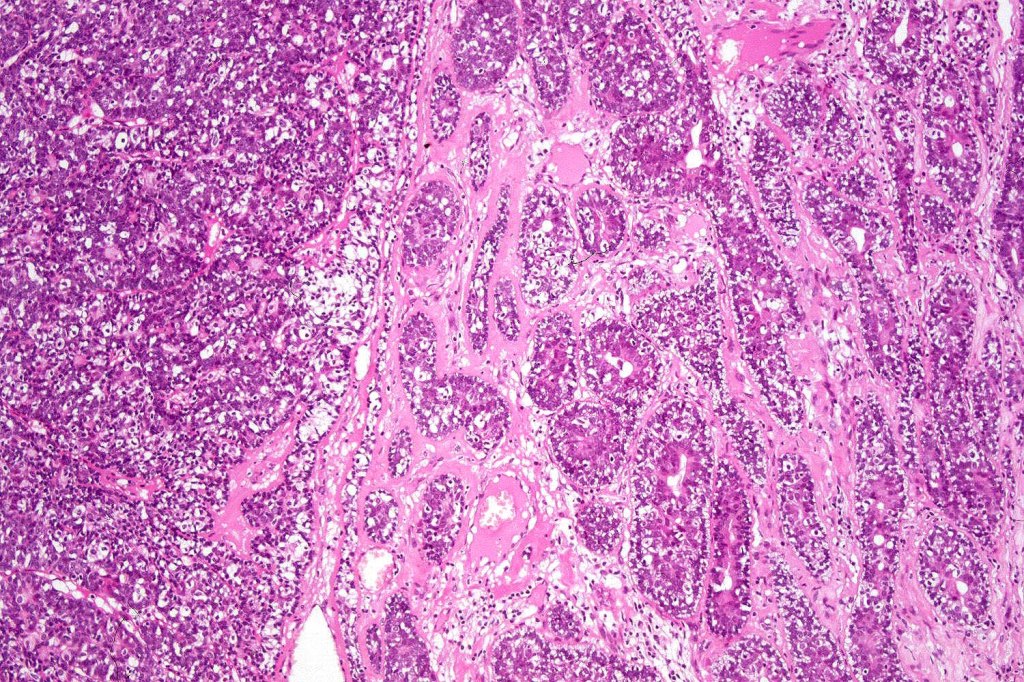

Histological features

•Pre-existent spiradenoma

•Malignant component shows loss of dual cell population, increased mitotic activity, atypical mitoses & necrosis

•Perineural infiltration & LVI may be present

•2. Salivary gland type basal cell adenocarcinoma-like pattern, high grade (BCAC-HG)